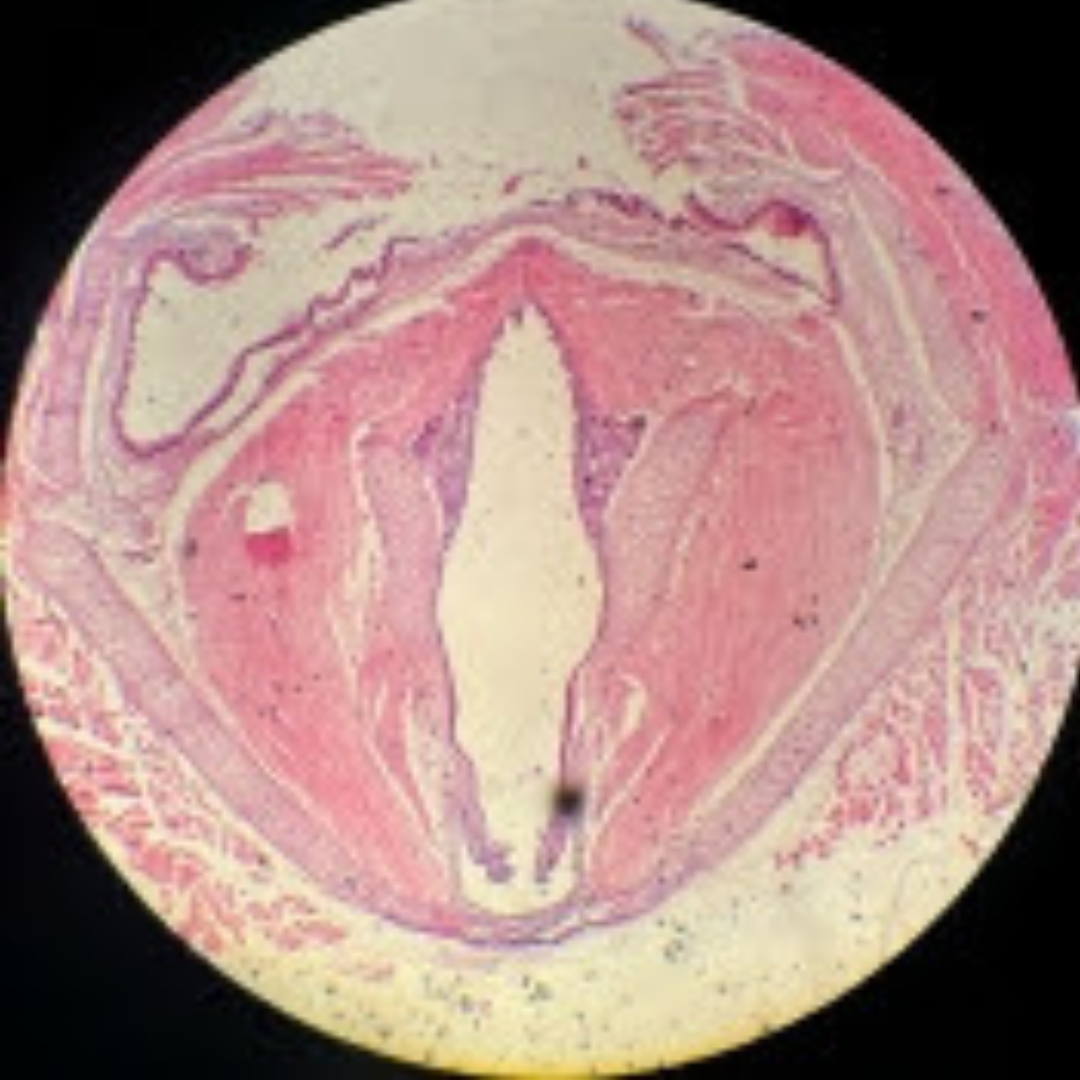

Cardiac Muscle

Cardiac Muscle

Cardiac Muscle

Cardiac Muscle

Cardiac Muscle